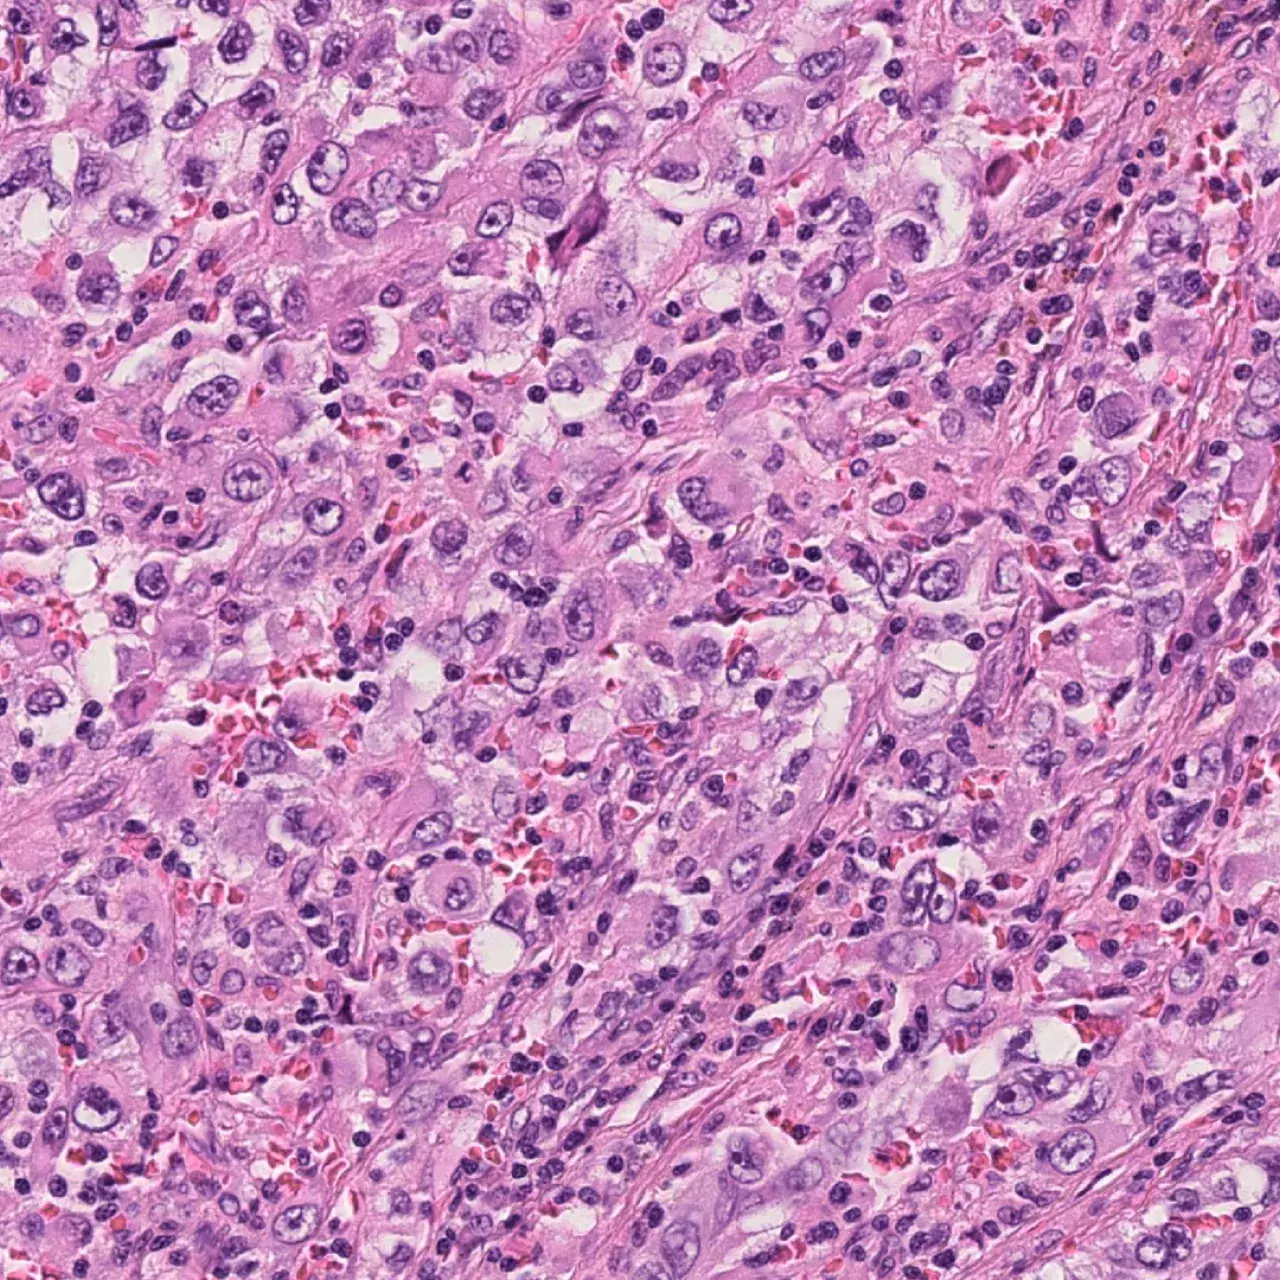

L'essor d'un vaccin innovant contre le mélanome, fondé sur la technique de l'ARN messager (ARNm ), pourrait marquer un tournant prometteur dans la lutte contre le cancer de la peau. Avec des résultats préliminaires indiquant une réduction de 65% du risque de récidive et de décès, cette innovation pourrait non seulement transformer le traitement du cancer de la peau, mais aussi ouvrir de nouvelles voies dans le traitement d'autres maladies graves. Les HUG participent à la troisième et dernière phase d’essais cliniques sous la supervision du Pr Olivier Michielin, chef du Département d’oncologie.